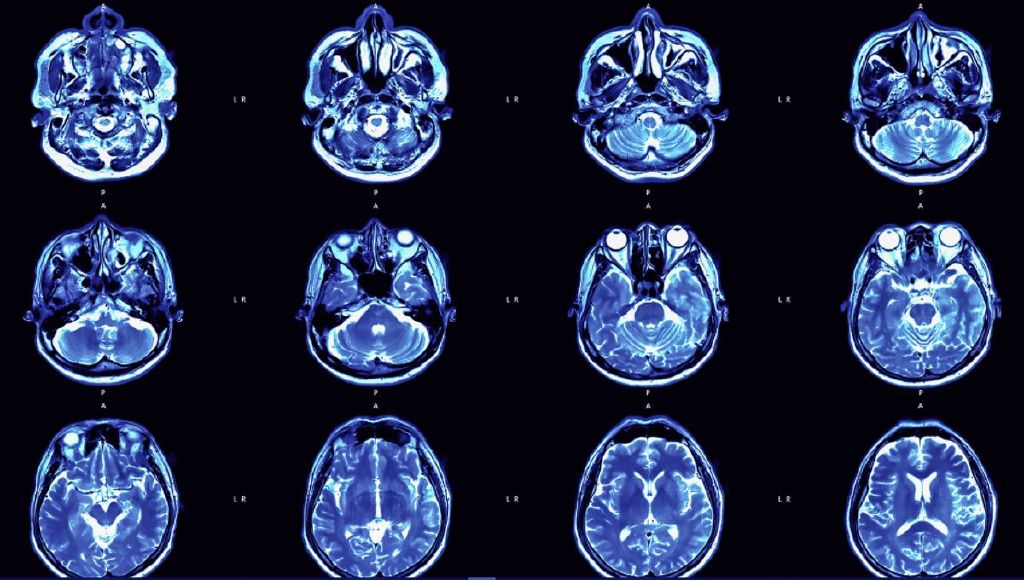

Brain Abscesses Have Skyrocketed In US Children In Last 2 Years, CDC Says

Cases have risen since the easing of pandemic restrictions.